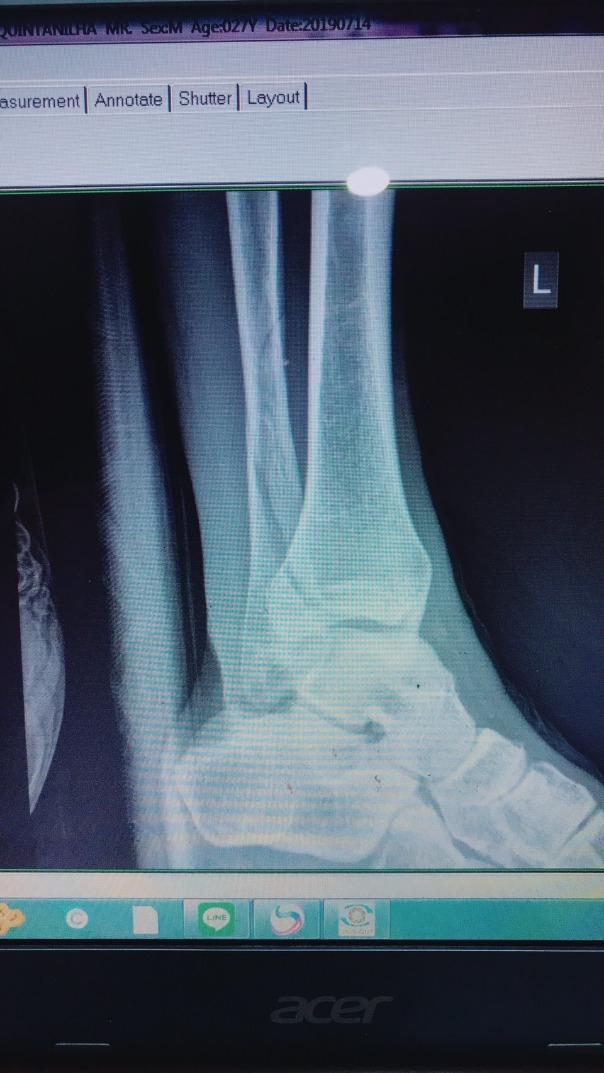

“พญาไก่ชน”หนองบัวพิชญ เอฟซี ทีมอันดับ 10 แห่งศึกไทยลีก 2 ล่าสุดต้องเจอกับข่าวร้ายเมื่อ โรดริโก้ มารันเยา ดาวยิงชาวบราซิล ที่เพิ่งประเดิมลงสนามช่วยทีมนัดแรก ในเกมบุกพ่ายระยอง เอฟซี 0-1 เมื่อวันที่ 14 ก.ค ที่ผ่านมา ได้รับบาดเจ็บหนักข้อเท้าแตก จนต้องเข้ารับการผ่าตัดด่วน และส่งผลให้เจ้าตัวต้องปิดเทอมยาว หมดสิทธิ์ลงสนามช่วยทีมไปจนจบฤดูกาลแน่นอนแล้ว